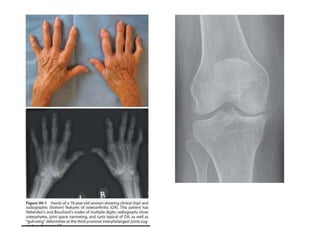

X-ray changes

1. Joint space narrowing

2. Subchondral sclerosis

3. Osteophytes

4. Cysts

X-ray changes 1. Jointspace narrowing 2. Subchondral sclerosis 3. Osteophytes 4. Cysts